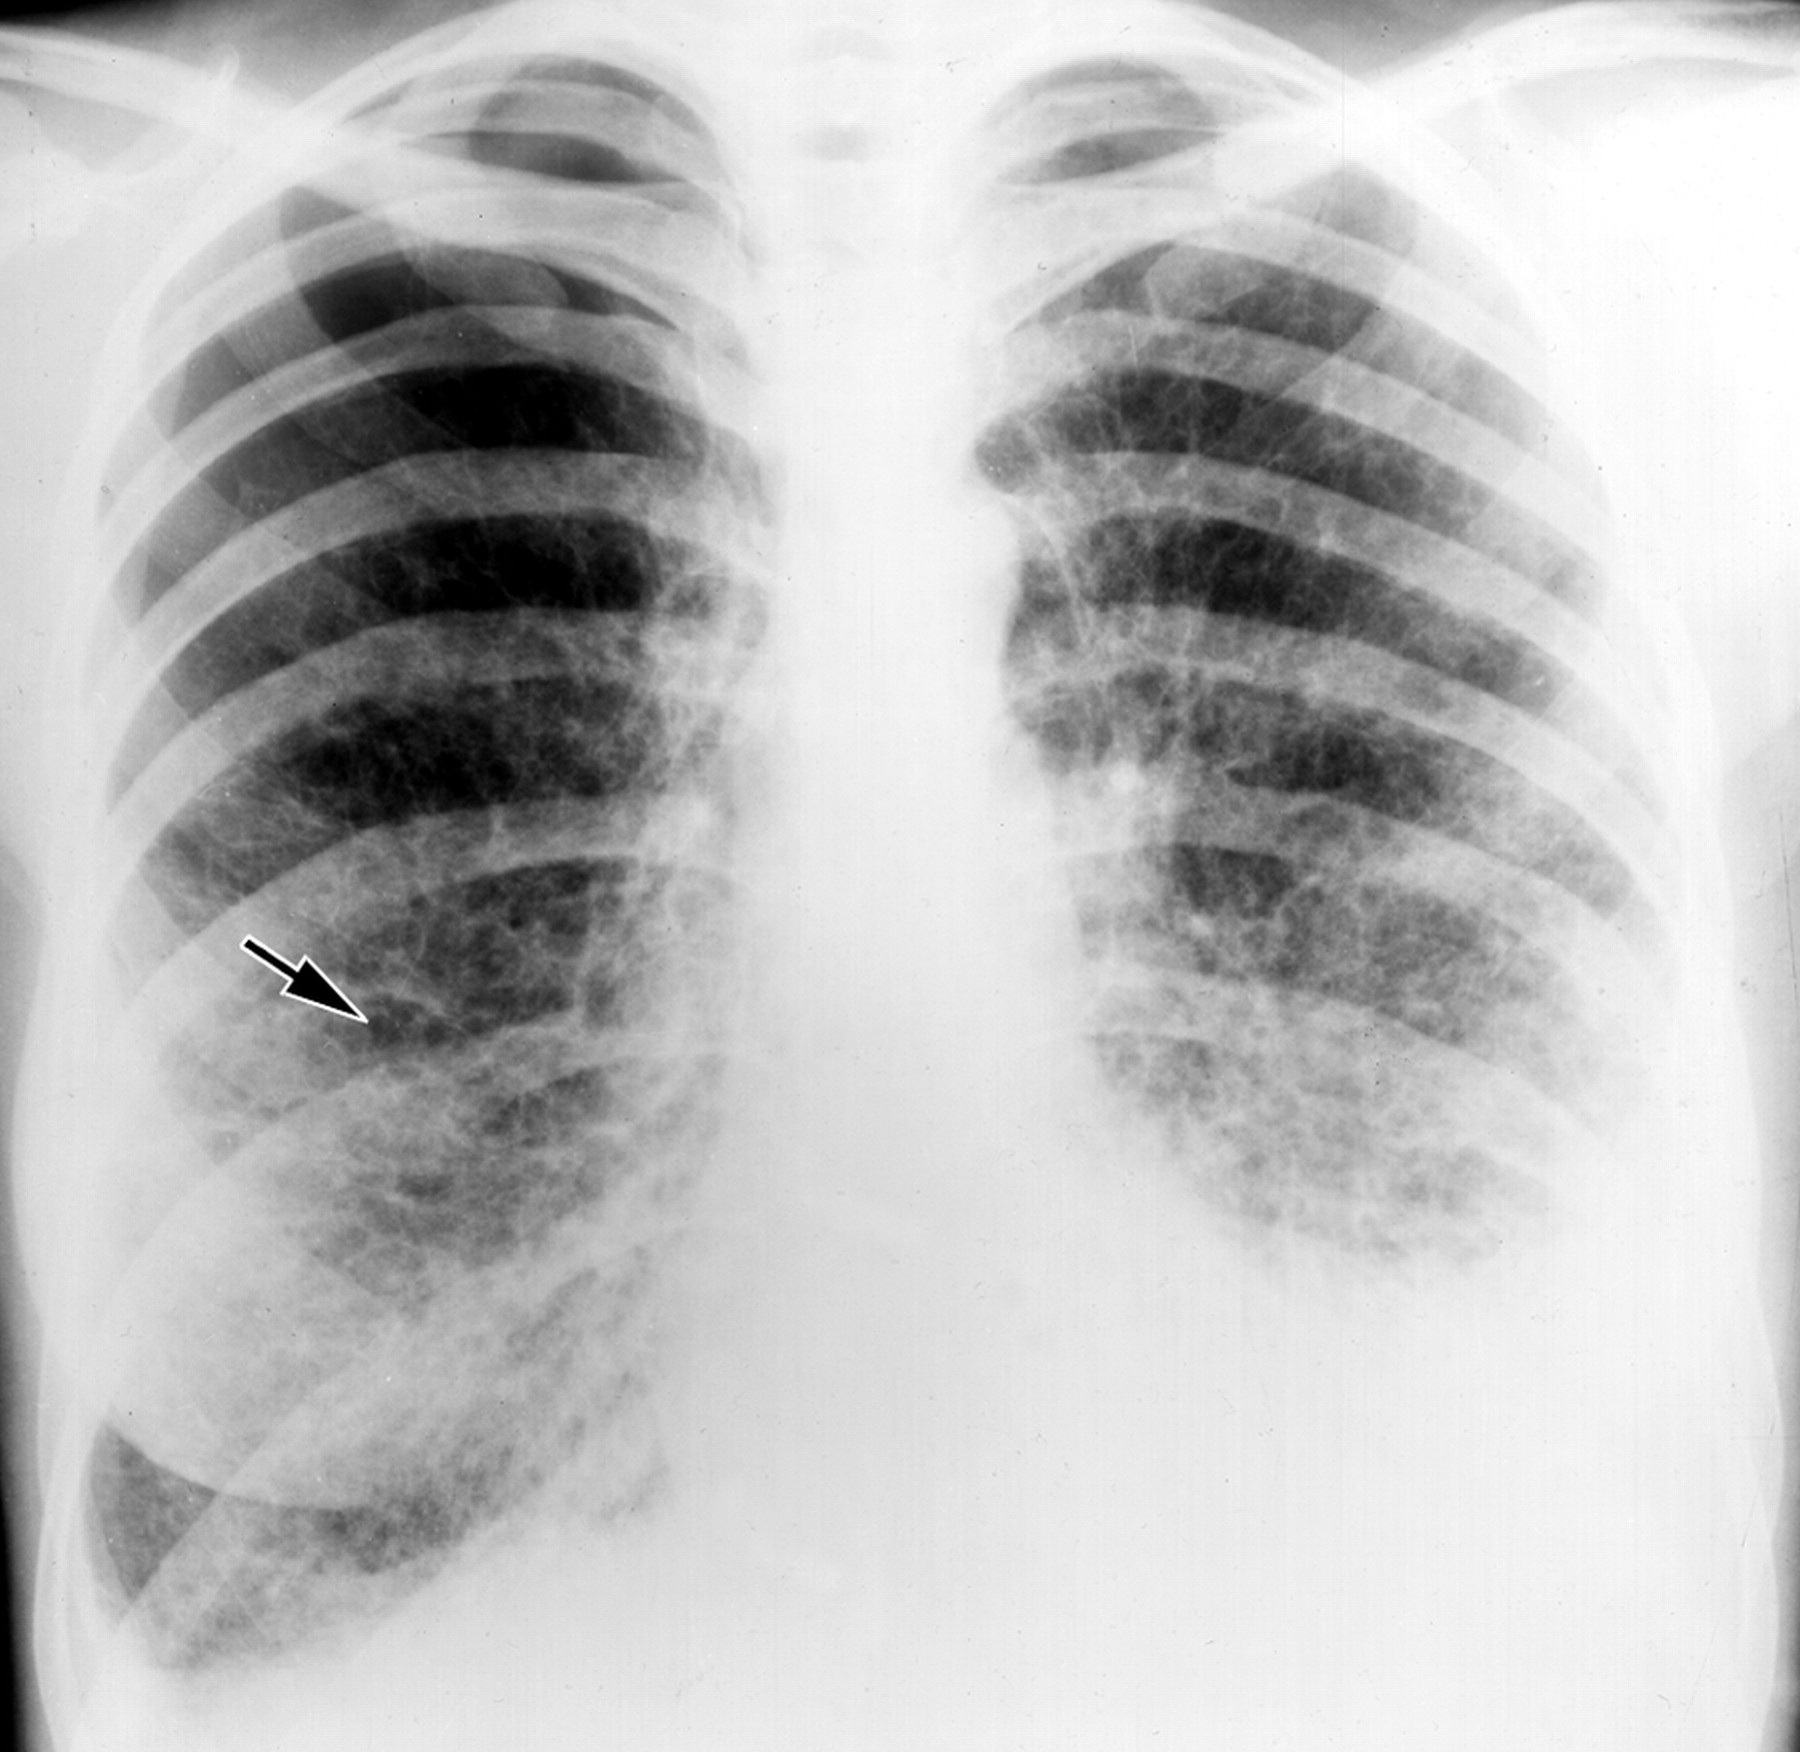

При поступлении одышка, кашель, Т до 37. "Рентгенкартина пневмонии справа, пневмосклероз, эмфизема. Киста, булла слева?" Прошу прощение за качество, снимки"с рук".

По "просьбам трудящихся" не выкладываю все сразу. Но уж ОЧЕНЬ эмфизема, режимы выдал - экспонометр("на среднего"), проявка - автомат. Снимки в реале - темнее ночи. Что тут больше всего смущает справа?

На фоне эмфиземы и булл имеется размытая интенсивная инфильтрация в S8 справа и гидроторакс в наддиафрагмальной зоне. НО... Уровень-то горионтальный, значит есть сообщение с воздухом. Пути два: снаружи (пункция) и изнутри (прорыв буллы, абсцесса, кисты). На реформатах жидкости нет.

И еще вопрос: где на РГ центральный-то? рак. Только небольшое расширение и кальцинаты левого корня.

Добавила аксиалы с видео в начале темы. По КТ: ну, буллы, ну, компрессия нижней доли и неполная - средней. Гидропневмоторакс справа. Эмфизема. Рака не увидела.

Ну, рака бы я конечно не поставил. КТ-признаки эмфиземы легких, буллезной эмфиземы, пневмогидроторакса в переднем отделе справа; сзади справа, считаю большая киста/кисты с уровнем жидкости.